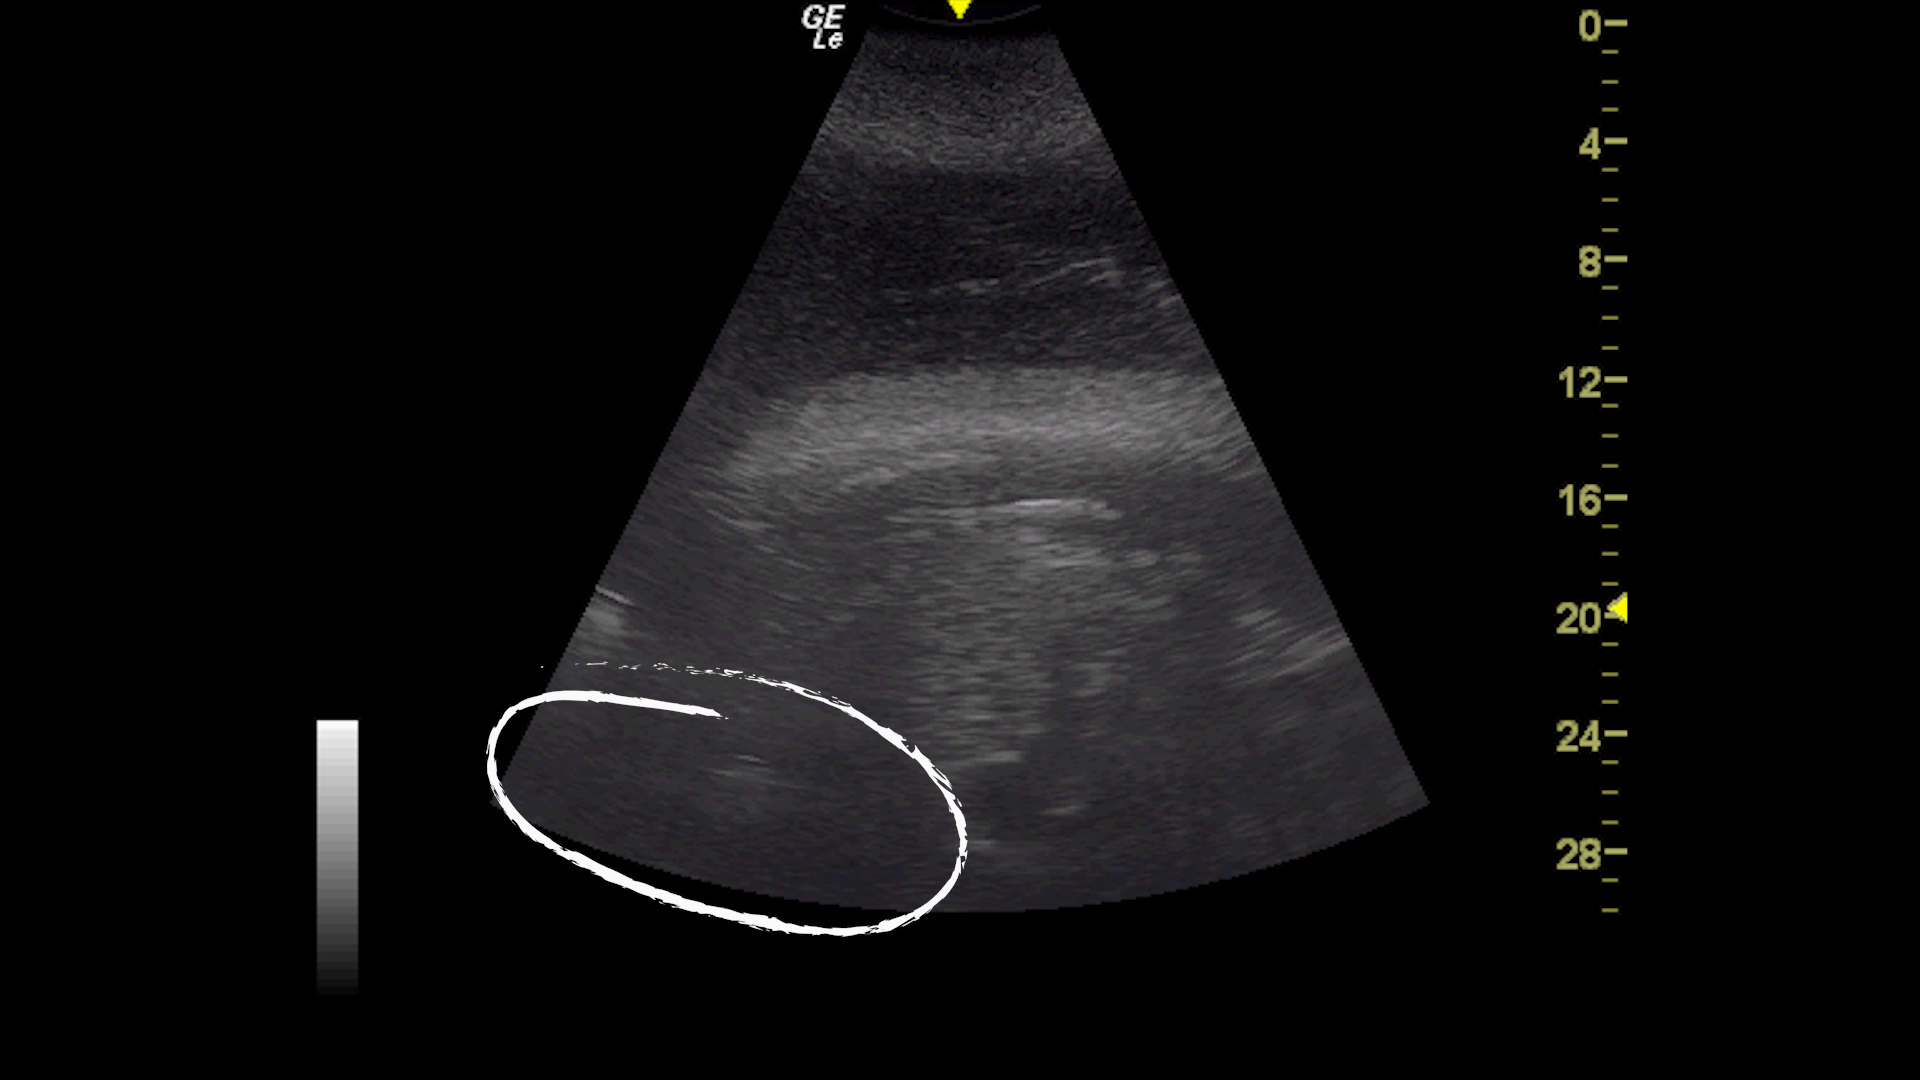

Die Pflege und die Routine des medizinischen Trainings der Orcas im Loro Parque wurde in den Schwangerschaftsmonaten intensiviert. Das hat zu einer lückenlosen Überwachung des Fötus und einer kontinuierlichen Kontrolle seiner Entwicklung geführt. „Wir führen praktisch zwei Mal pro Woche eine Ultraschalluntersuchung mit einem Hochfrequenzsystem durch, das keinerlei Auswirkungen auf den Fötus hat und keine Schmerzen verursacht“, erklärt Dr. Almunia.

Diese Ultraschalluntersuchungen haben es den Tierärzten erlaubt zu sehen, dass der Fötus sich in einer guten Position befindet, das Herz schlägt und alles, funktioniert, wie es sollte. Deshalb bereitet sich das Personal des Parks derzeit darauf vor, zu erfahren, wann der genaue Geburtszeitpunkt sein wird. „Und wir bereiten uns auch darauf vor, im Falle, dass etwas schief läuft, alles parat zu haben, um sofort intervenieren zu können“, hebt der Direktor der Stiftung hervor. Das ist deshalb besonders relevant, weil in der Natur 50% der Orca-Jungtiere vor dem Erreichen des ersten Lebensjahres sterben. Dazu kommt das Handicap, dass Morgan taub ist.